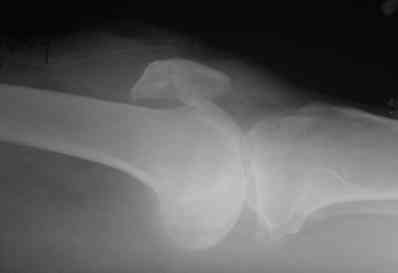

po moemu na snimke viden avascul necrosis of talar bone . lechit v cootvetstvii .

Надо "трогать". Подтаранный артродез очень показан и синтез перелома так же.

не согласен с последним оратором :)

показание к подтаранному артродезу ( как и к артродезу голеностопа) только одно - сильнейшая боль в стопе. Артродез - дело стремное, и больному надо четко объяснить, что то, что делается - это последняя мера, позволяющая избежать ампутации, и что следующая операция после артродеза стопы, если он будет неудачным - ампутация. так что , на мой взгляд , правильная тактика по поводу тарана - объяснить больному всю правду по поводу стопы и предложить приходить на операцию, когда боль в стопе не позволит ему ходить даже с палочкой.

Уважаемый Абдурашид!Что касается перелома таранной кости - нет возможности сделать КТ?С чем связана хромота?По-видимому,пациента в первую очередь беспокоит боль при ходьбе,видимо,придется делать артродез.